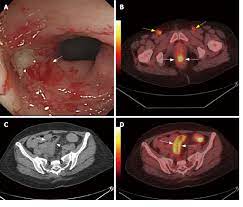

Automated Visual Evaluation Ave For Cervical Cancer Screening from www.hpvworld.com Various strains of the human papillomavirus (hpv), a sexually transmitted infection, play a role in causing most cervical cancer. Invasive cervical cancer is the third most common gynecologic malignancy (, 1).there were approximately 13,700 new cases and 4,900 deaths in 1998 with an estimated prevalence of 208,000 (, 2).patients present with abnormal vaginal bleeding and can have pelvic pain from local spread of disease or inflammation (, 3).eighty percent to 90% of cervical carcinomas are of squamous cell. Cervical cancer stage ib2 and ib3. And within a stage, an earlier letter means a lower stage. Cancer of the uterine cervix, the portion of the uterus that is attached to the top of the vagina. Cancer of the uterine cervix, the portion of the uterus that is attached to the top of the vagina. Infographic for 8 alarming signs of cervical cancer in flat design. Cervical cancer diagnosis on the clipboard.